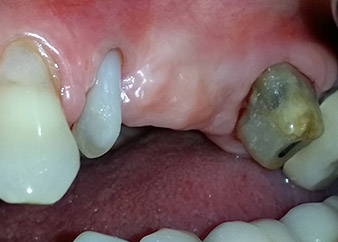

apical periodontal lesion at tooth 24

Fig. 1: 58-year-old patient. Preoperative radiograph showing an apical periodontal lesion at tooth 24 and horizontal loss of alveolar bone in the second quadrant.

A 58-year-old female patient complained of pain and increased mobility of her bridge abutment tooth 24. Periodontal inflammation was present with pocket depths of 7 mm mesiobuccally and more than 12 mm distally, as well as third-degree furcation involvement. Moreover, the radiograph revealed an extensive periodontal lesion around the apical region of the (alio loco) endodontically pretreated tooth 24 (Fig. 1).

One year earlier, teeth 25 and 26 had been extracted due to trauma and for endo-perio reasons, prior to the placement of the bridge. A combined endo-perio lesion was diagnosed for tooth 24, of unclear aetiology. The patient wanted to keep her bridge abutment teeth 24 and 27 and would not accept a final, or even temporary, removable prosthesis. Therefore, it was agreed to make all efforts to retain both teeth, in spite of their poor prognosis as based on radiological and clinical findings.